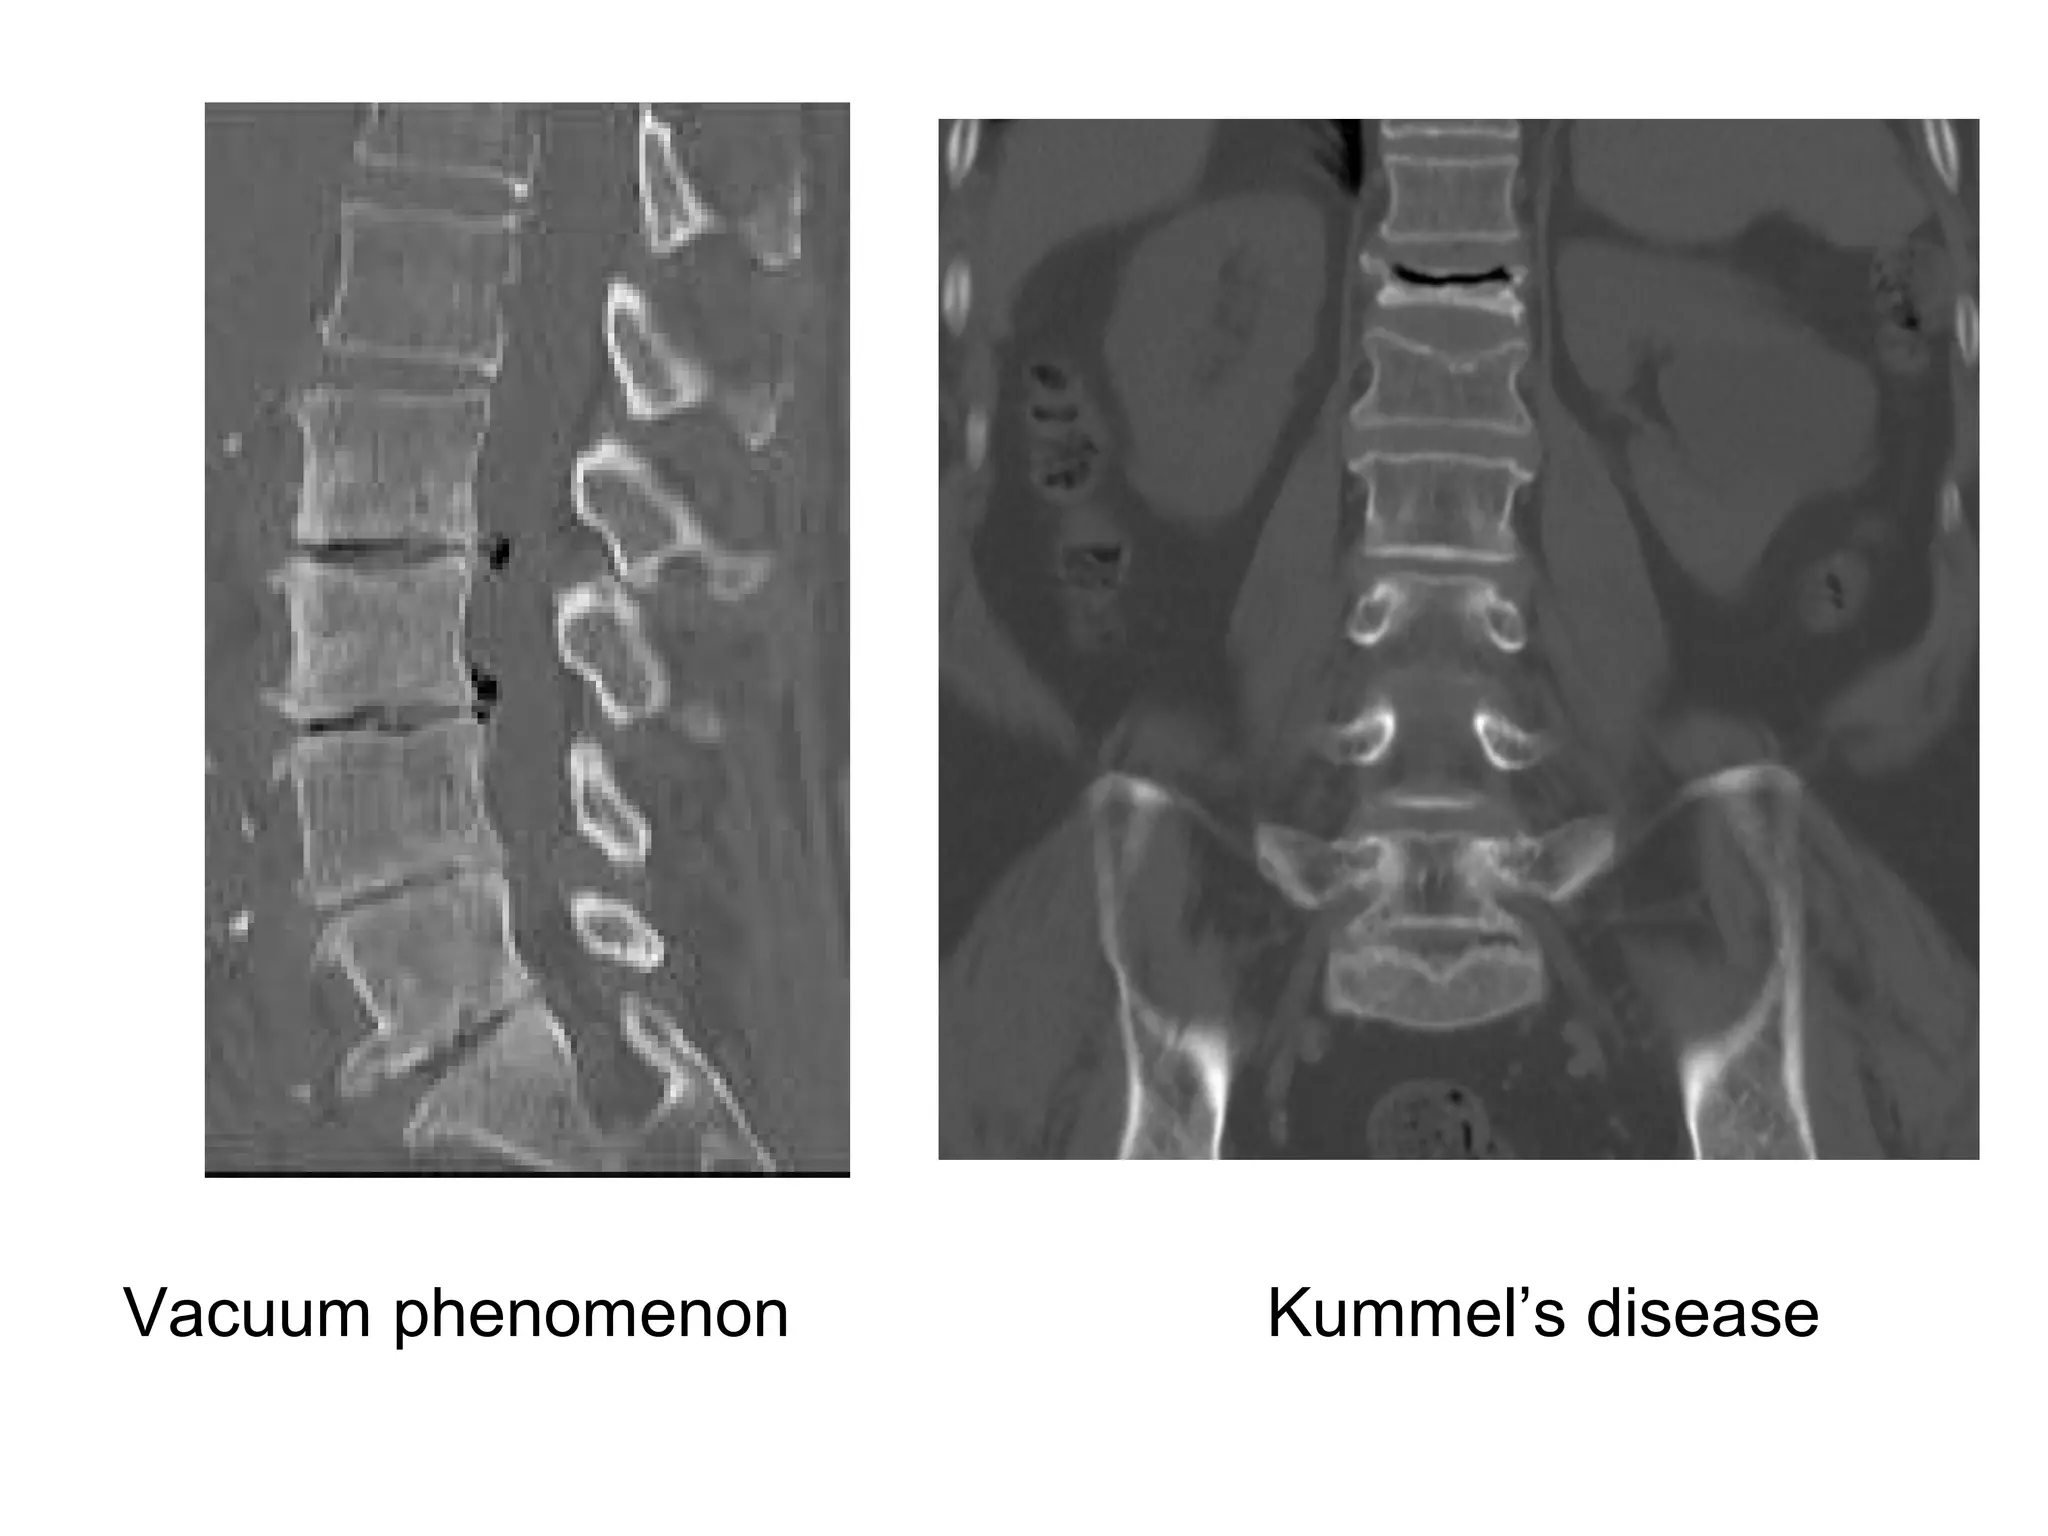

**N.B. :

-It is important not to confuse vacuum

phenomenon (gas in intervertebral disc) with

Kummel disease which is gas in a vertebral body

compression fracture representing

osteonecrosis

Vacuum phenomenon Kummel’s disease